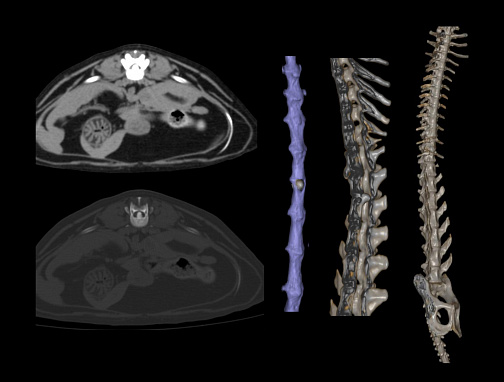

SinoVision AlphaCT 358 Plus — компьютерный томограф на 64 среза. Устройство позволяет получать изображения высокой чёткости с помощью современной интеллектуальной платформы.

Универсальный томограф AlphaCT 358 Plus позволяет получать изображения высокой чёткости.

• 64 среза

• Большая диафрагма 75 см

• Мощность генератора 32 кВт

• Толщина среза от 0,3125 мм

• Интеллектуальная система обработки изображения

• Патентованный детектор V-PIXEL